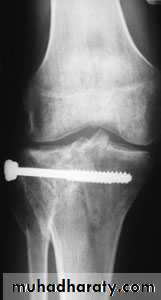

Treatment:

Undisplaced fractures

treated conservatively:

Haemarthrosis aspiration and compression bandaging,

above knee cast for one months

followed by functional brace and physiotherapy.

For displaced fractures

treatment is by open reduction and internal fixation with

plate and screws as it is an intra articular fracture.

fixation of tibial plateau fracture